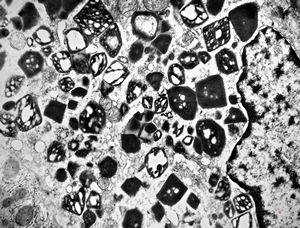

M,58y. | crystalline inclusions in hepatocyte after unknown medication